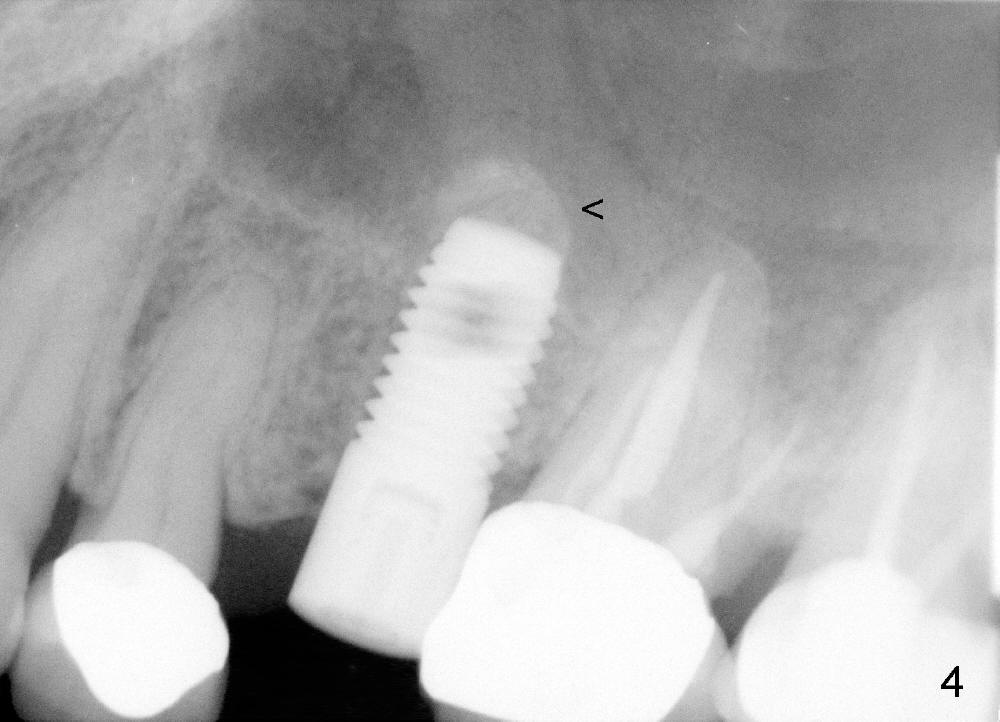

A 59-year-old lady used to have a 3-unit bridge in the upper left quadrant. A 4.5x6mm Bicon implant (Fig.1 B without extruding into the sinus) was placed in the atrophic pontic area 5 months earlier. When the abutment (A) was removed, the implant came out. The osteotomy was processed with a 4.5x14 mm tapered tap, which was unstable. When a 4.8 mm cylindrical tap was placed (past the sinus floor), it was tight (Fig.2). A 5x14 mm cylindrical implant (Fig.3 I) was inserted with elevation of the apparent sinus floor (>, no allograft used in case of sinus infection). Seven months postop, the density of sinus floor increases (Fig.4 <). The implant is stable and processed for crown (Fig.5 C, different view of the lifted sinus floor (<)). While sinus floor density is decreasing, the mesial and distal bone density is increasing 6 months (Fig.6), 1 year 6 months (Fig.7) and 3 year 6 months (Fig.8) post cementation.